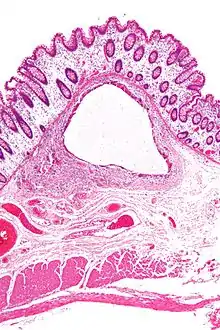

اسْترواح الأَمعاء (بالإنجليزية: intestinal pneumatosis أو Pneumatosis intestinalis)[1] كما يعرف أيضاً باستِرواح الكِيْسات المعوِيَّة (pneumatosis cystoides intestinalis)[2] هو وجود غير طبيعي للهواء أو لغاز آخر في الأمعاء، مما ينتج عنه تشكل كيسات غازية في جدار الأمعاء.[3][4] كعلامة شعاعية، فإنه يشير بقوة إلى الالتهاب المعوي القولوني الناخر. هذا على عكس الغاز الموجود في تجويف الأمعاء (الذي يُخفف عند اطلاق الريح). في الأطفال حديثي الولادة، يعتبر استرواح الأمعاء تشخيصًا للالتهاب المعوي القولوني الناخر،[5] ويتم إنتاج الغاز بواسطة البكتيريا في جدار الأمعاء.[6] لا تزال إمراضية الاسترواح المعوي غير مفهومة جيدًا ومن المحتمل أن يكون متعدد العوامل. لا يعتبر استرواح الأمعاء بحد ذاته مرضًا، بل هو علامة سريرية. في بعض الحالات، يكون نتيجة عرضية، بينما في حالات أخرى، ينجذر بحالة داخل البطن تهدد الحياة.